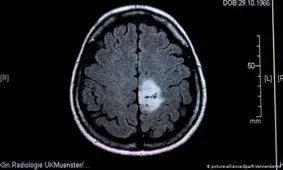

آباکسیژنه ماده قوی و نافذ است و غلظت بالای آن میتواند به بافت سلولها آسیب برساند و سبب رشد غیرقابل کنترل سلولهای…